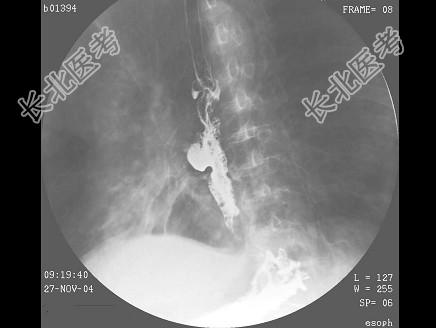

- 单项选择题男,71岁, 脾大、腹水、肝管结石2年,结合图像, 最可能的诊断为 ( )

E、食管癌